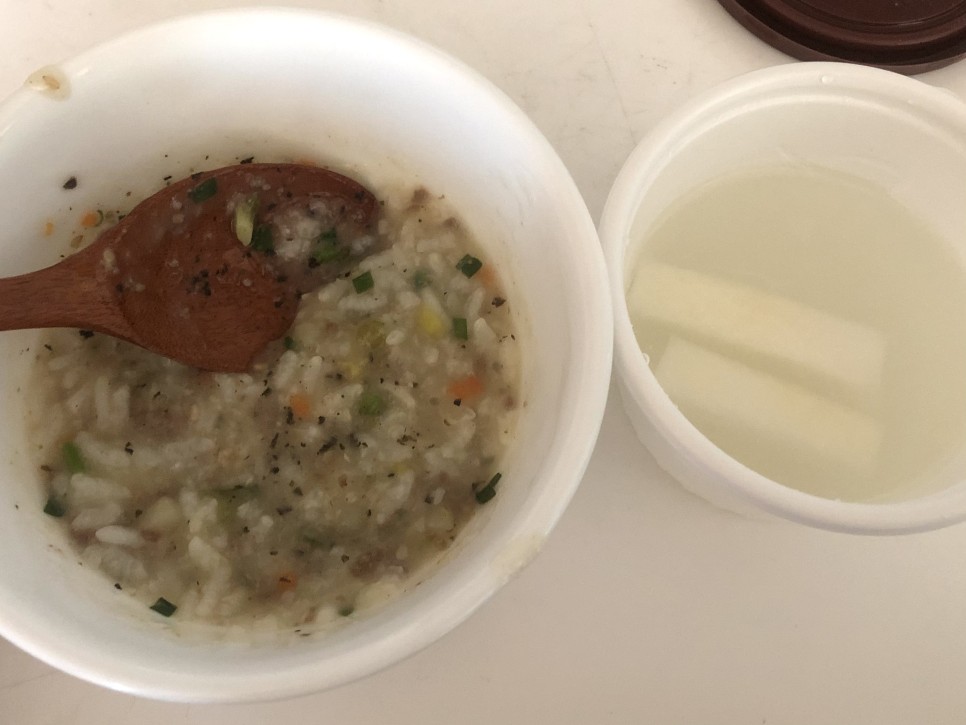

수술 이틀째의 아침

엄마가 쌀 씻어서?끓여주신 죽인데 간이 돼 있어서 이것만 먹어도 괜찮았어요( ´ ; ω ; ` )

그리고 계란찜인데 저렇게 잘게 부셔서 입 안에서도 완전 갈아서? 넘겨줬습니다…wwwww

근데 목이 너무 아파서 거의 못 먹었어요.밑에 얼음팩은 음식을 차게 하려고 놓았어요.

수술 이틀째의 점심 식사

이것은 진짜 죽에서 사온 야채죽이지만, 쌀알이 꽤 크기 때문에 몇 번이나 씹다가 그만두었습니다.( ´ ; ω ; ` )

그런데 이것도 거의 못 먹었어요.잘 먹지 않으면 출혈이 생기지 않는다고 했습니다만 ㅠㅠ